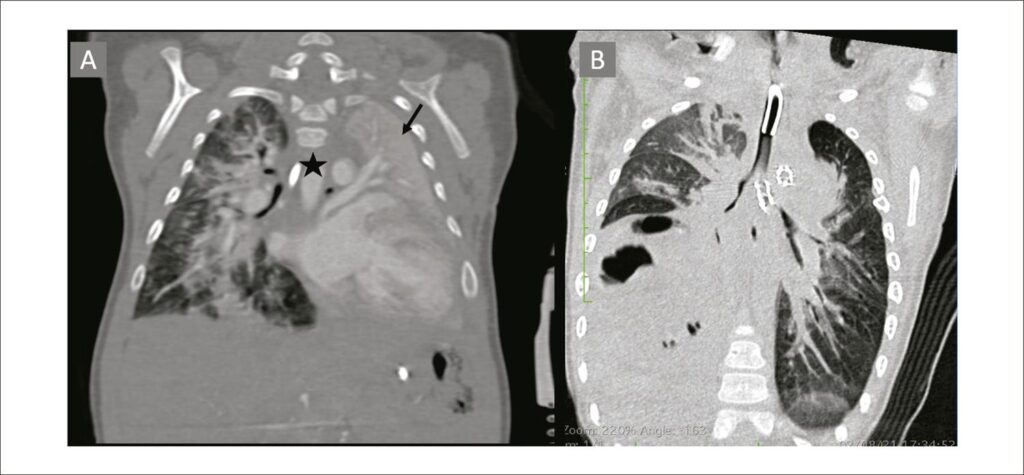

Expandable Airway Stents: Success in the Extrinsic Bronchial Compression Approach After Reconstruction of the Aortic Arch

The interruption of the aortic arch is a rare congenital cardiopathy, whose surgical correction generally requires reconstruction of the aortic arch. This intervention can cause distortion of the aortopulmonary space and results in bronchial compression with a consequent pulmonary atelectasis and dependence on ventilatory assistance. The most commonly used therapeutic options for bronchial decompression are not always enough to make pulmonary expansion possible. Our study presents a case of the implant of an endoluminal stent in an infant who, in the post-operative stage of the correction of the interruption of the aortic arch, developed complete atelectasis of the left lung secondary to bronchial compression, with no response after posterior aortopexy